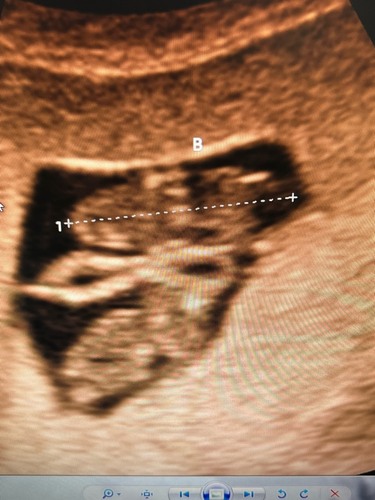

Ik heb precies hetzelfde gehad. Afgelopen vrijdag extra echo gekregen (6+5) en alles was goed. De vk vertelde dat wanneer je zwanger bent, je bloedvaten zichter op de huid liggen, door niezen, lachen of zelfs al door gewoon lopen zou er eens een adertje kunnen knappen. Niks om je zorgen over te maken! De vk vertelde dat wanneer je echt donker rood bloed verliest, het nodig is om aan de bel te trekken 鉂わ笍